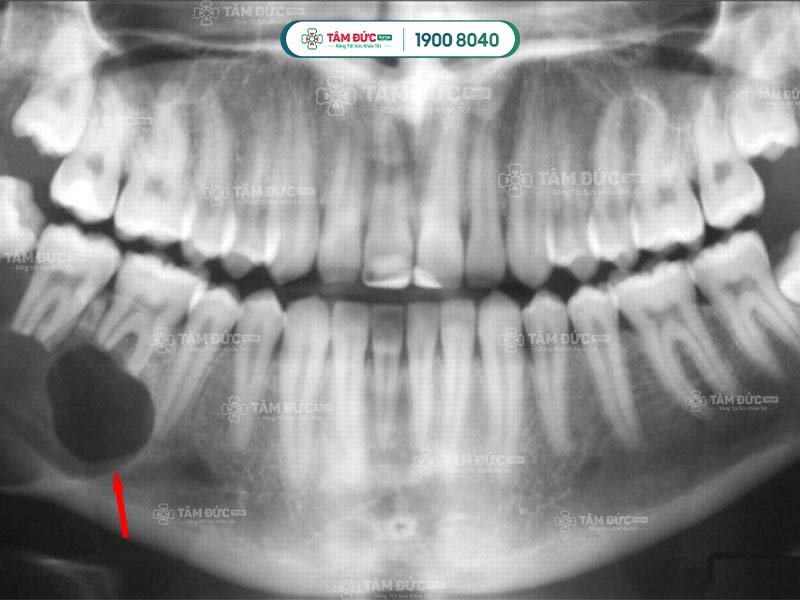

Với phương pháp này, bác sĩ cần loại bỏ hoàn toàn các mô tủy bị chết trong răng. Bác sĩ dùng dung dịch chuyên dụng để làm sạch ống tủy, trám ống tủy bằng vật liệu chuyên dụng. Đôi khi Quý khách cần phải lấy tủy nhiều lần để điều trị triệt để bệnh lý.

Vi khuẩn trú ngụ trong tủy răng có thể thoát ra ngoài thông qua lỗ sâu răng. Tiếp đến, chúng có thể tấn công vào sâu chân răng, làm cho tình trạng viêm nhiễm nghiêm trọng hơn.

Theo thời gian, cấu trúc chân răng bị phá vỡ dẫn đến viêm xương hàm. Các triệu chứng ở tình trạng này ngày 1 dữ dội hơn, làm cho sức khỏe và tinh thần của Quý khách bị ảnh hưởng nghiêm trọng.